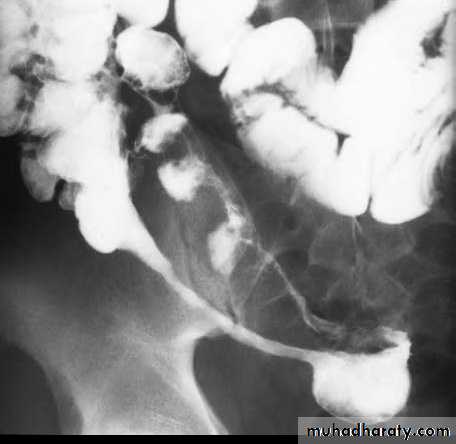

A long segment of narrowed ileum (string sign) is present with proximal ileal dilation& caecal contraction

TI

caecum